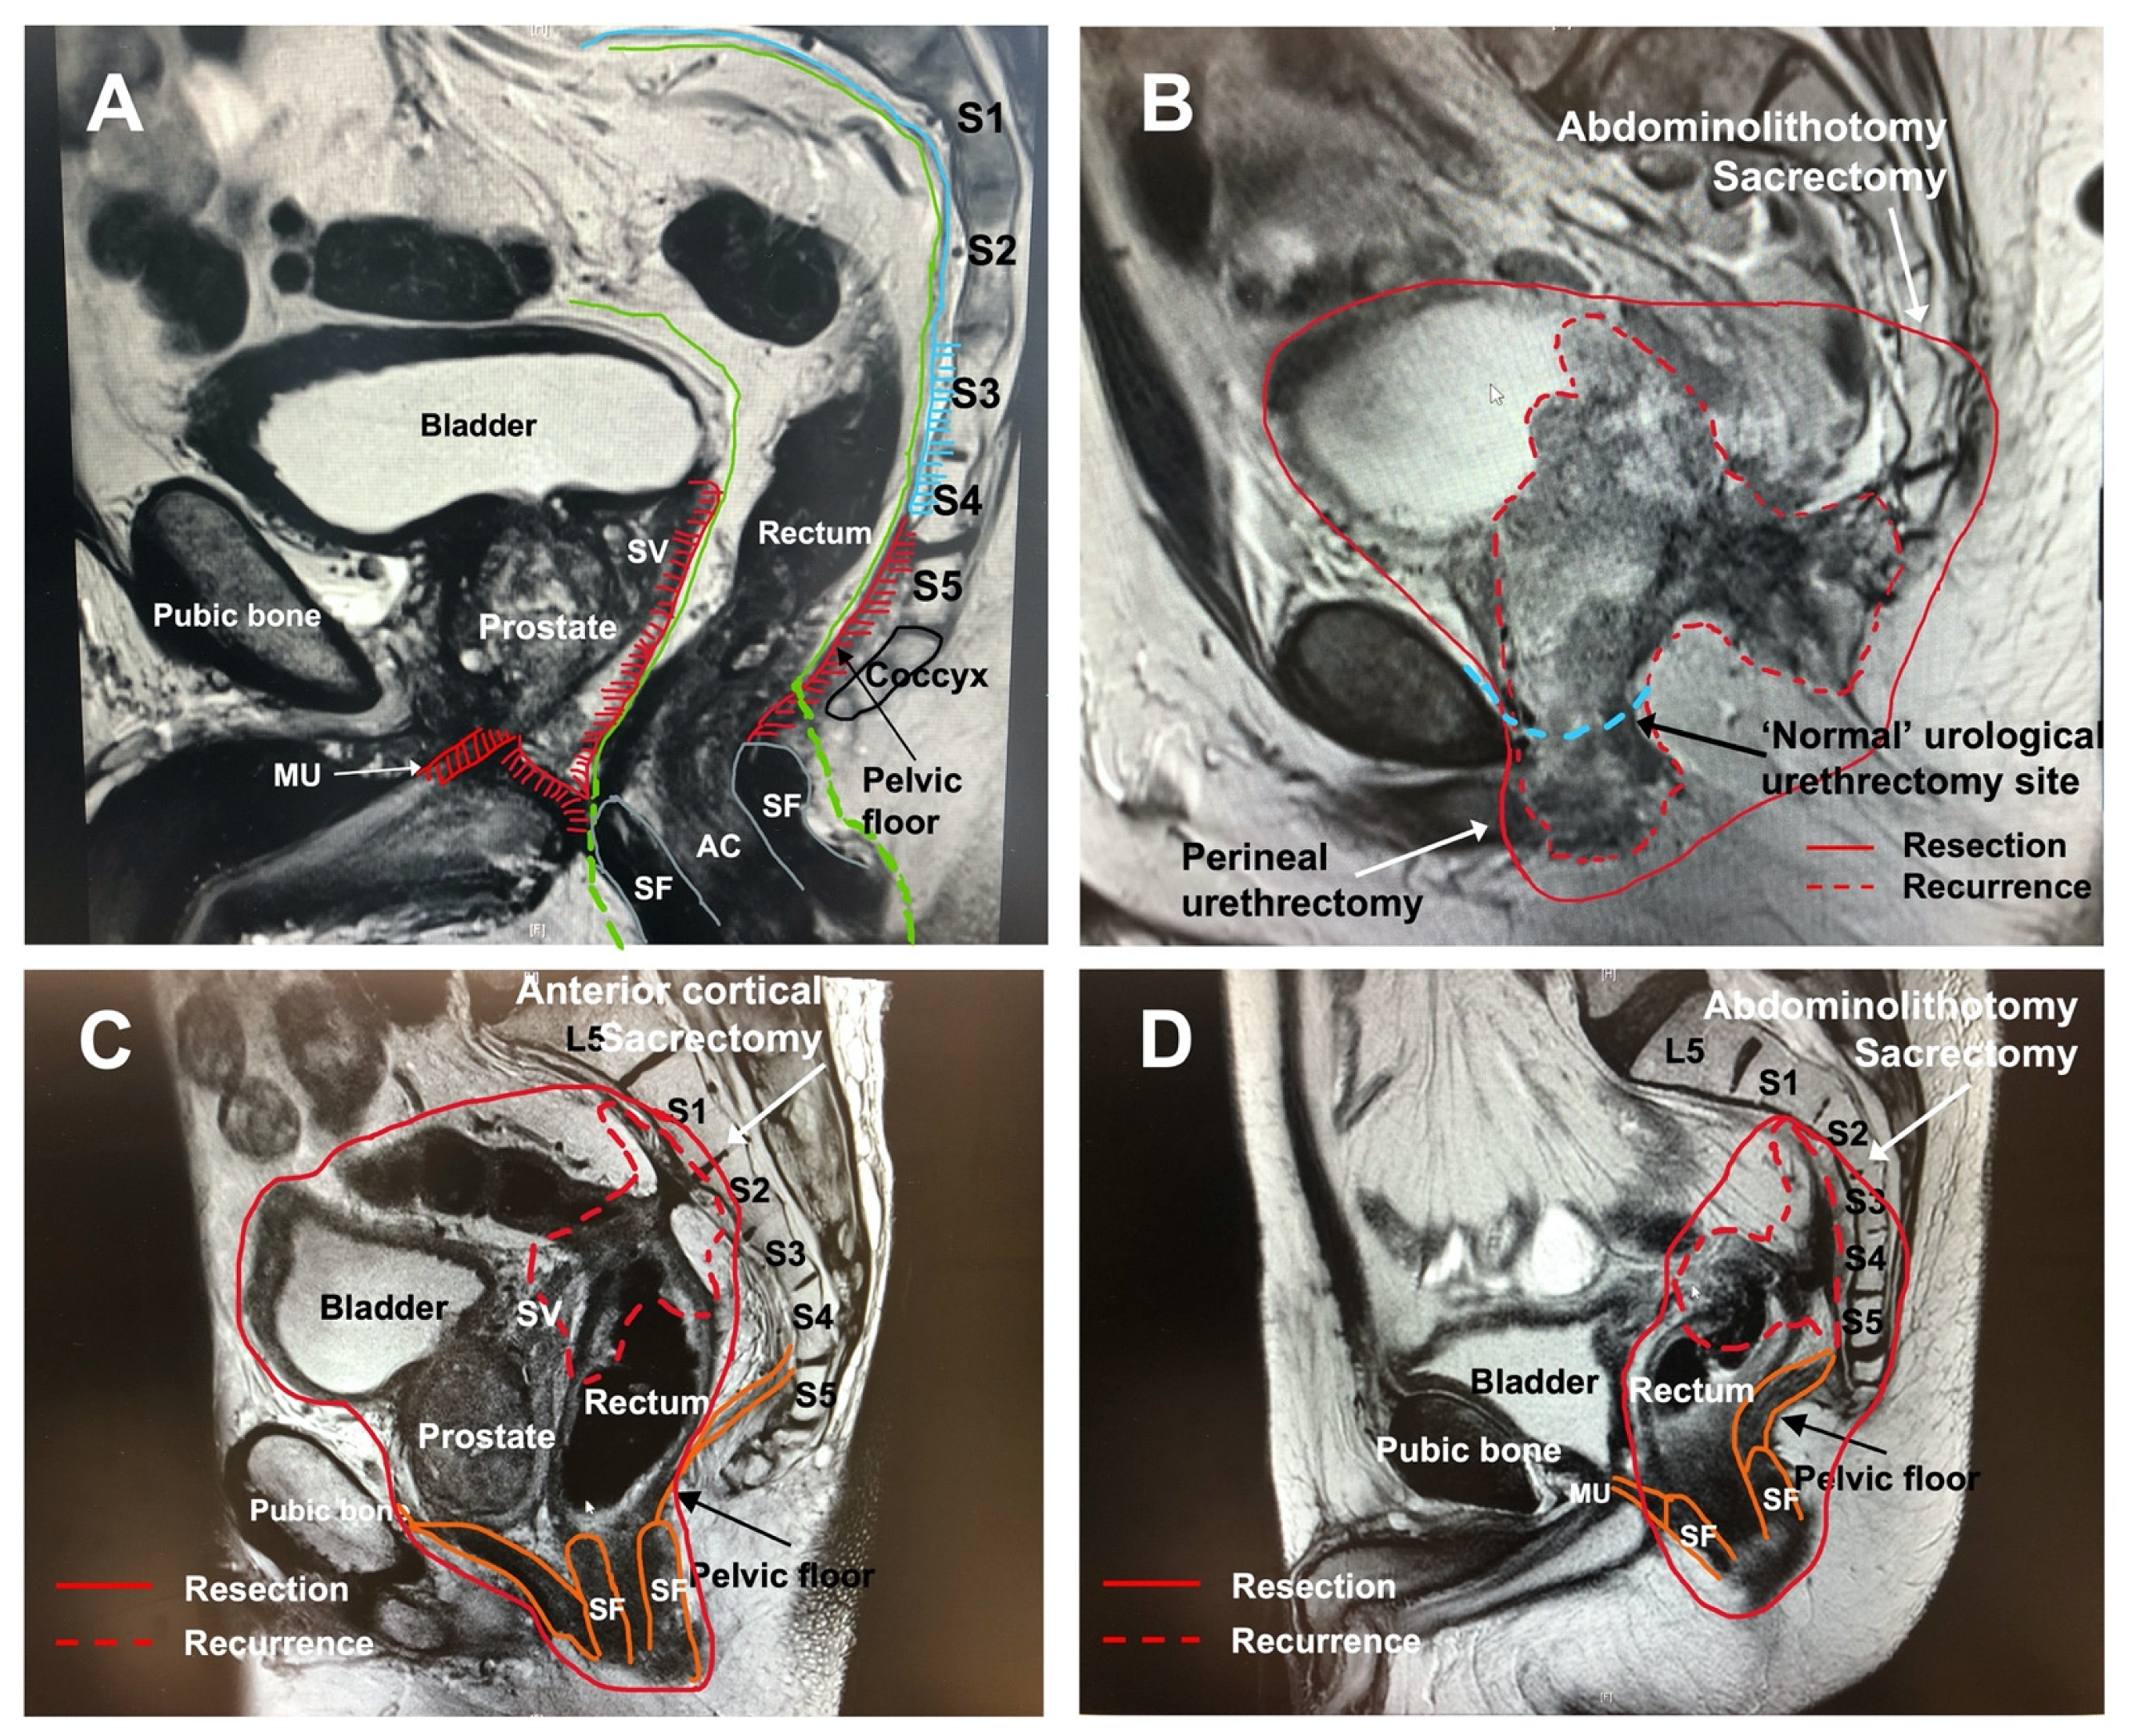

4.1. The Anterior Compartment with or without En-Bloc Pubic Bone Resection

4.2. The Posterior Compartment and En-Bloc Sacrectomy